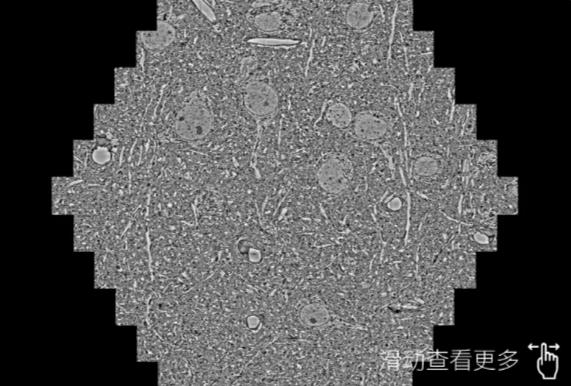

鼠脑切片。左图使用新疆蔡司新疆扫描电镜MultiSEM706对165μmx143pm面积区域成像,耗时仅需1.5秒。右图为鼠脑切片中30μm区域放大效果。样品由芝加哥大学B.Kasthuri提供。

使用蔡司高速新疆扫描电镜MultiSEM对1mm²人脑皮层组织进行高分辨成像,并对其中的各种细胞结构进行三维重构分析。左图展示了2x3mm²组织平面中锥体神经元的三维重构效果。右图显示了局部体积神经元三维重构。图像由哈佛大学chtman实验室提供,渲染图由D. Berger 制作。